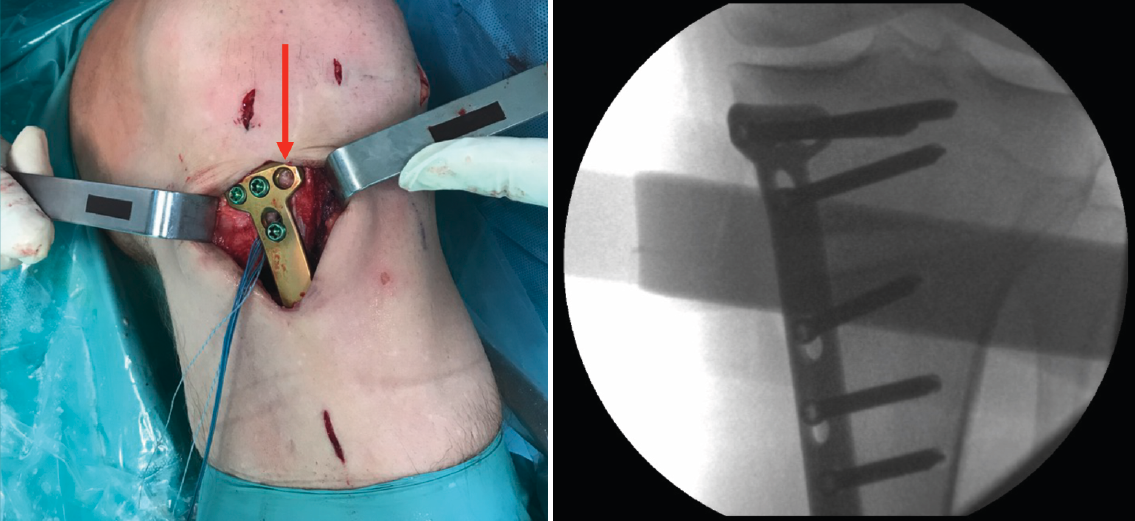

Figura 1. A: colocación del paciente con rodilla a 90° de flexión. Se marca la incisión de aproximadamente 4-6 cm que servirá para la extracción de los isquiotibiales y la osteotomía tibial alta; B: extracción de isquiotibiales para realizar la plastia.

Se marca sobre la piel la línea de incisión de 4-6 cm en la cara medial de la tibia proximal, aproximadamente 1,5 a 2 cm por debajo de la interlínea articular (Figura 1A). Una de las ventajas de esta osteotomía es que no precisa disecar e inestabilizar el ligamento colateral medial (LCM). El corte se realiza entre las dos inserciones del LCM y la placa se coloca por encima de este ligamento. De esta manera, la rodilla sigue estable aunque se decida realizar una retirada de la placa una vez consolidada la osteotomía.

Figura 2. Colocación de aguja guía: punto de entrada en la unión metafisodiafisaria tibial dirigida hacia la cabeza del peroné.

Una vez disecado el plano subcutáneo, se identifica la pata de ganso y se extraen los isquiotibiales según la técnica habitual de cada cirujano (Figura 1B). Bajo control radioscópico, se coloca la aguja guía aproximadamente medio centímetro por encima de la pata de ganso orientada hacia la cabeza del peroné, según la técnica clásica de osteotomía biplanar (Figura 2). Se marcan los cortes de la osteotomía biplanar y se realiza primero el corte vertical por encima de la tuberosidad tibial, con una inclinación de aproximadamente 120° respecto a la osteotomía de apertura llegando hasta la cortical lateral (Figura 3).

Figura 4. Colocación de escoplos de forma progresiva para realizar la apertura (una vez realizados los cortes con la sierra).

Una vez hecho el túnel tibial, se introduce la plastia y se fija a nivel femoral y tibial (Figura 7). Si se utiliza una plastia de isquiotibiales, los autores recomiendan una fijación femoral cortical de suspensión regulable, dejando unos milímetros para el ajuste final después de la colocación de la placa de osteotomía. Una vez fijada la plastia, se procede a la colocación de la placa de osteotomía TomoFix® (Synthes, Oberdorf, Switzerland) para la tibia proximal medial (Figura 8). En la mayoría de los casos el tornillo más anterior coincide con el túnel tibial de RLCA, motivo por cual no se coloca (Figura 9).

Figura 5. A: medición del ángulo de apertura de la osteotomía con el medidor; B: colocación del distractor en la parte posterior de la osteotomía, evitando así el aumento de la pendiente tibial posterior.

Figura 7. Introducción de la plastia a través del túnel tibial, manteniendo el distractor en posición.

Figura 8. Colocación de la placa TomoFix® para la tibia proximal medial una vez fijada la plastia de ligamento cruzado anterior a nivel femoral y tibial.

Figura 9. Fijación de la placa con tornillos. Se señala con la flecha la ausencia del tornillo más anterior, dada su coincidencia con el túnel tibial.